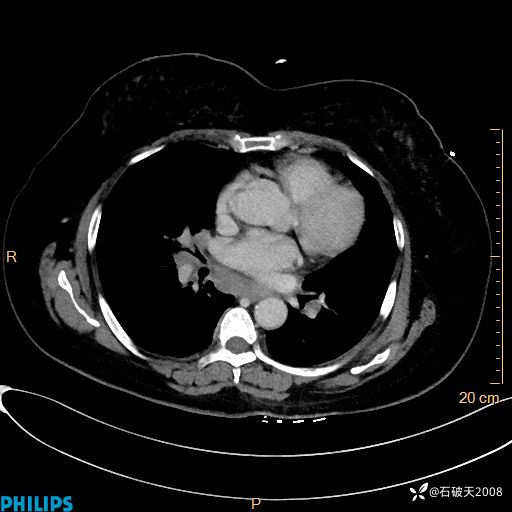

肺结节病?纵膈型肺癌?淋巴瘤?有点意思,欢迎围观

女 52岁 主 诉:咳嗽10余天,咳痰2天。

现病史:10余天前无明显诱因出现咳嗽,呈阵发性干咳,伴咽喉部发痒,无咽痛,无咳痰,无鼻塞、流涕、打喷嚏,无发热、畏寒、寒颤,无头痛、头晕,无胸闷、胸痛,无反酸、烧心,无腹痛、腹泻,无尿频、尿急,无皮疹等,在当地诊所求治,给予口服药物治疗(具体不详),病情无好转。遂在当地社区卫生服务中心开具口服药物治疗(具体不详),疗效欠佳。2天前出现咳痰,在我院门诊求治,行胸部CT提示肺部感染,建议住院,患者要求口服药物治疗,目前仍咳嗽、咳白色粘痰,白天量多,夜间自觉喉部喘鸣音,遂再次来院就诊,以“肺部感染”为诊断收入院。发病以来,神志清,精神可,饮食可,夜间睡眠差,大小便正常,近期体重无明显变化。

肺窗